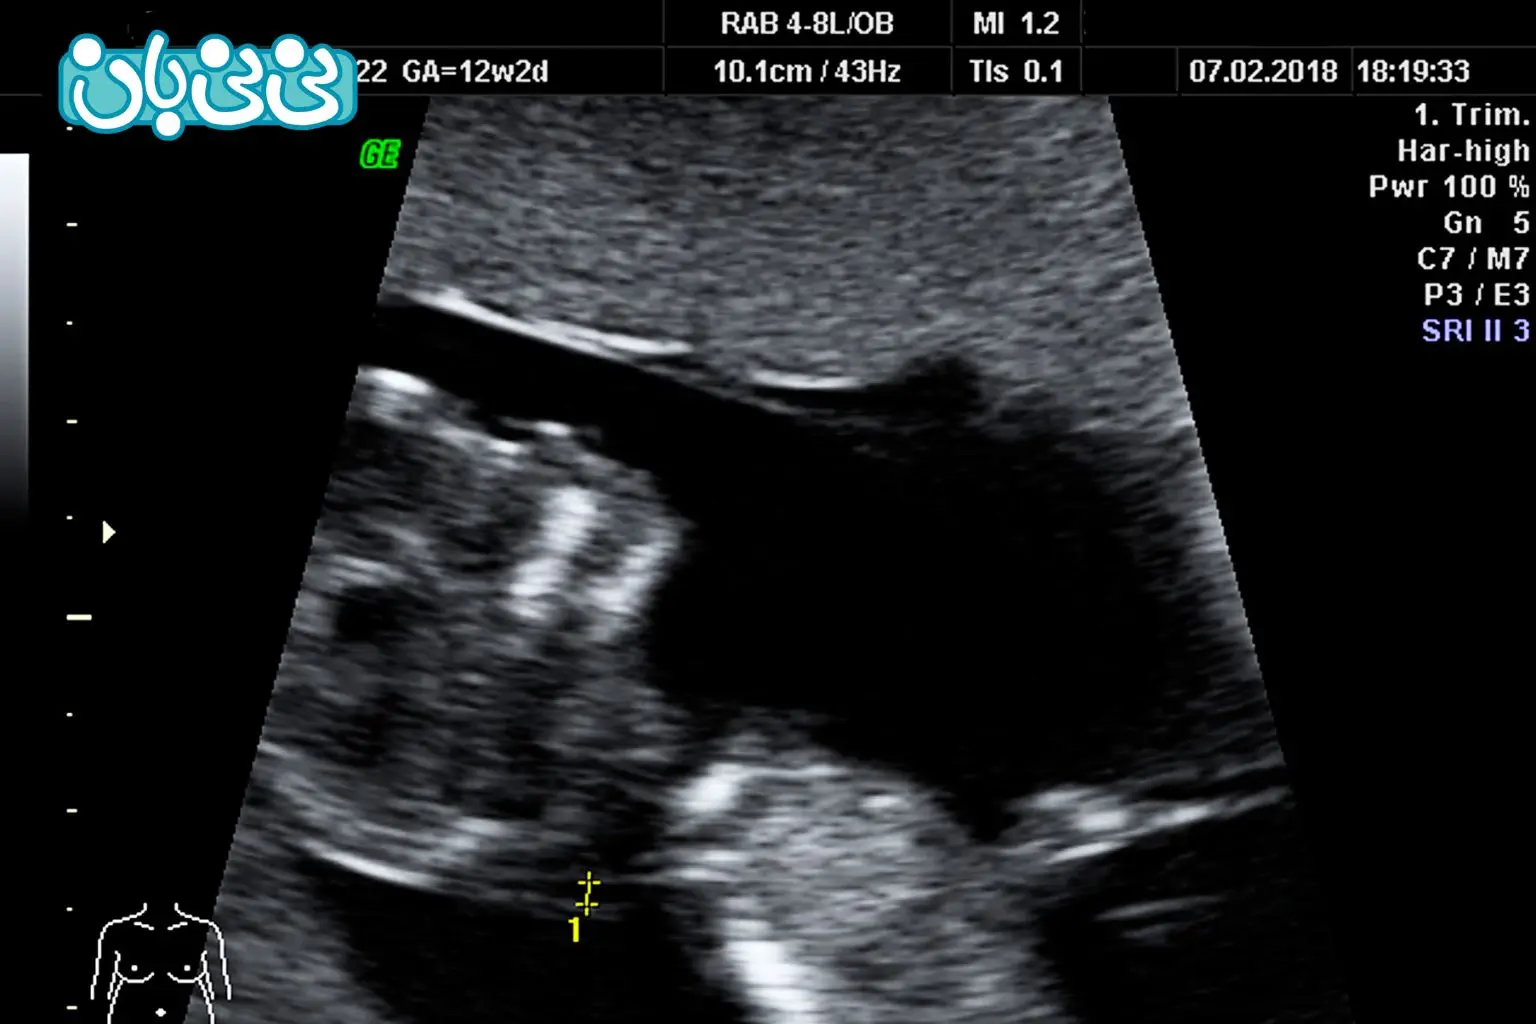

سونوگرافی nt (Nuchal Translucency) در سه ماهه اول بارداری مقدار مایع پشت گردن جنین را اندازهگیری میکند. وجود مقدار کمی مایع در این ناحیه طبیعی است و اندازهگیری آن به پزشکان کمک میکند احتمال وجود ناهنجاریهای کروموزومی یا ژنتیکی در جنین را تخمین بزنند. این آزمایش نوعی غربالگری است، نه تشخیص قطعی. فقط نشان میدهد آیا جنین در معرض خطر است یا خیر و آیا نیاز به آزمایشهای تکمیلی وجود دارد یا نه.

این سونوگرافی بین هفته ۱۱ بارداری تا ۱۳ بارداری یا زمانی که طول جنین از سر تا دنبالچه (CRL) بین ۴۵ تا ۸۴ میلیمتر باشد، انجام میشود. دلیل این محدودیت زمانی، این است که بعد از هفته چهاردهم بارداری، مایع پشت گردن جنین به تدریج توسط بدنش جذب میشود و اندازهگیری دقیق آن دشوار میشود. این آزمایش معمولاً بخشی از «غربالگری سه ماهه اول بارداری» است.

نحوه انجام سونو nt چگونه است؟

- معمولاً با سونوگرافی شکمی انجام میشود (در صورت نیاز واژینال).

- ژل روی شکم مالیده میشود و با پروب (دستگاه دستی) روی شکم حرکت داده میشود.

- تصاویر جنین روی مانیتور ظاهر میشود و ضخامت فضای پر از مایع پشت گردن جنین به میلیمتر اندازهگیری میشود.